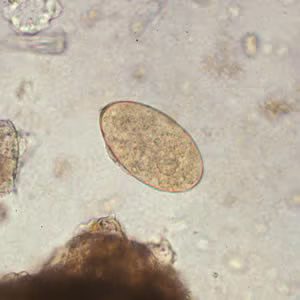

Fasciola hepatica eggs.

Eggs of Fasciola spp. are broadly ellipsoidal, are operculated, measure 130–150 µm long by 60–90 µm wide, and are passed unembryonated in feces. Fasciola spp. eggs can be difficult to distinguish from Fasciolopsis buski eggs, although the abopercular end of Fasciola spp. eggs often have a roughened or irregular area. Eggs are often reported as “Fasciola/Fasciolopsis” eggs due to morphologic overlap. Also, egg size cannot reliably distinguish F. hepatica from F. gigantica.